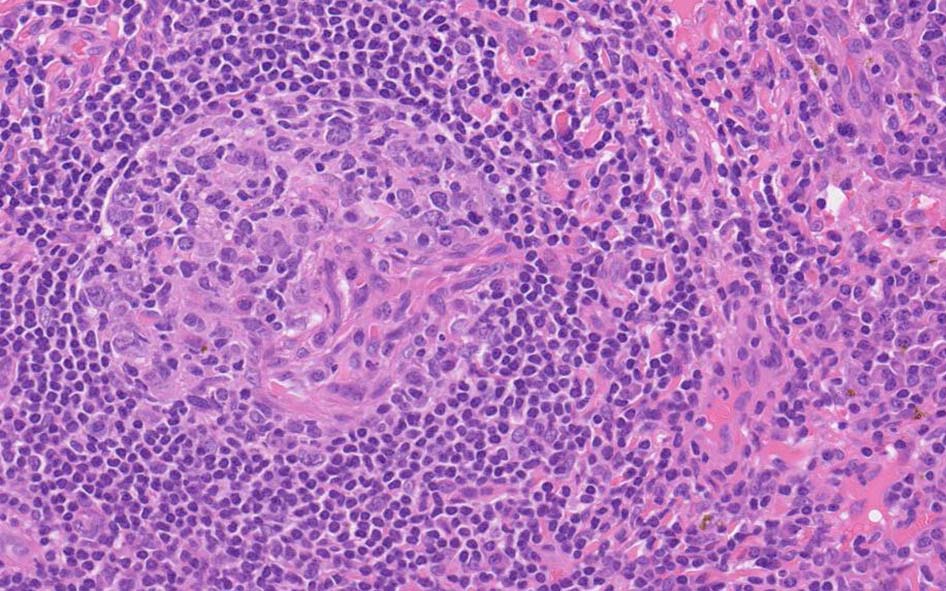

12 x 3.8mm, 腫大した鼠径リンパ節が生検された.--クリックで大きな画像がみられます.|

萎縮した胚中心をマントル細胞が取り囲む濾胞構造がびまん性に認められる. 濾胞間には,形質細胞が密に認められる.

萎縮した胚中心には細血管が侵入する特徴的な所見がある. (Lolli-pop germinal center)